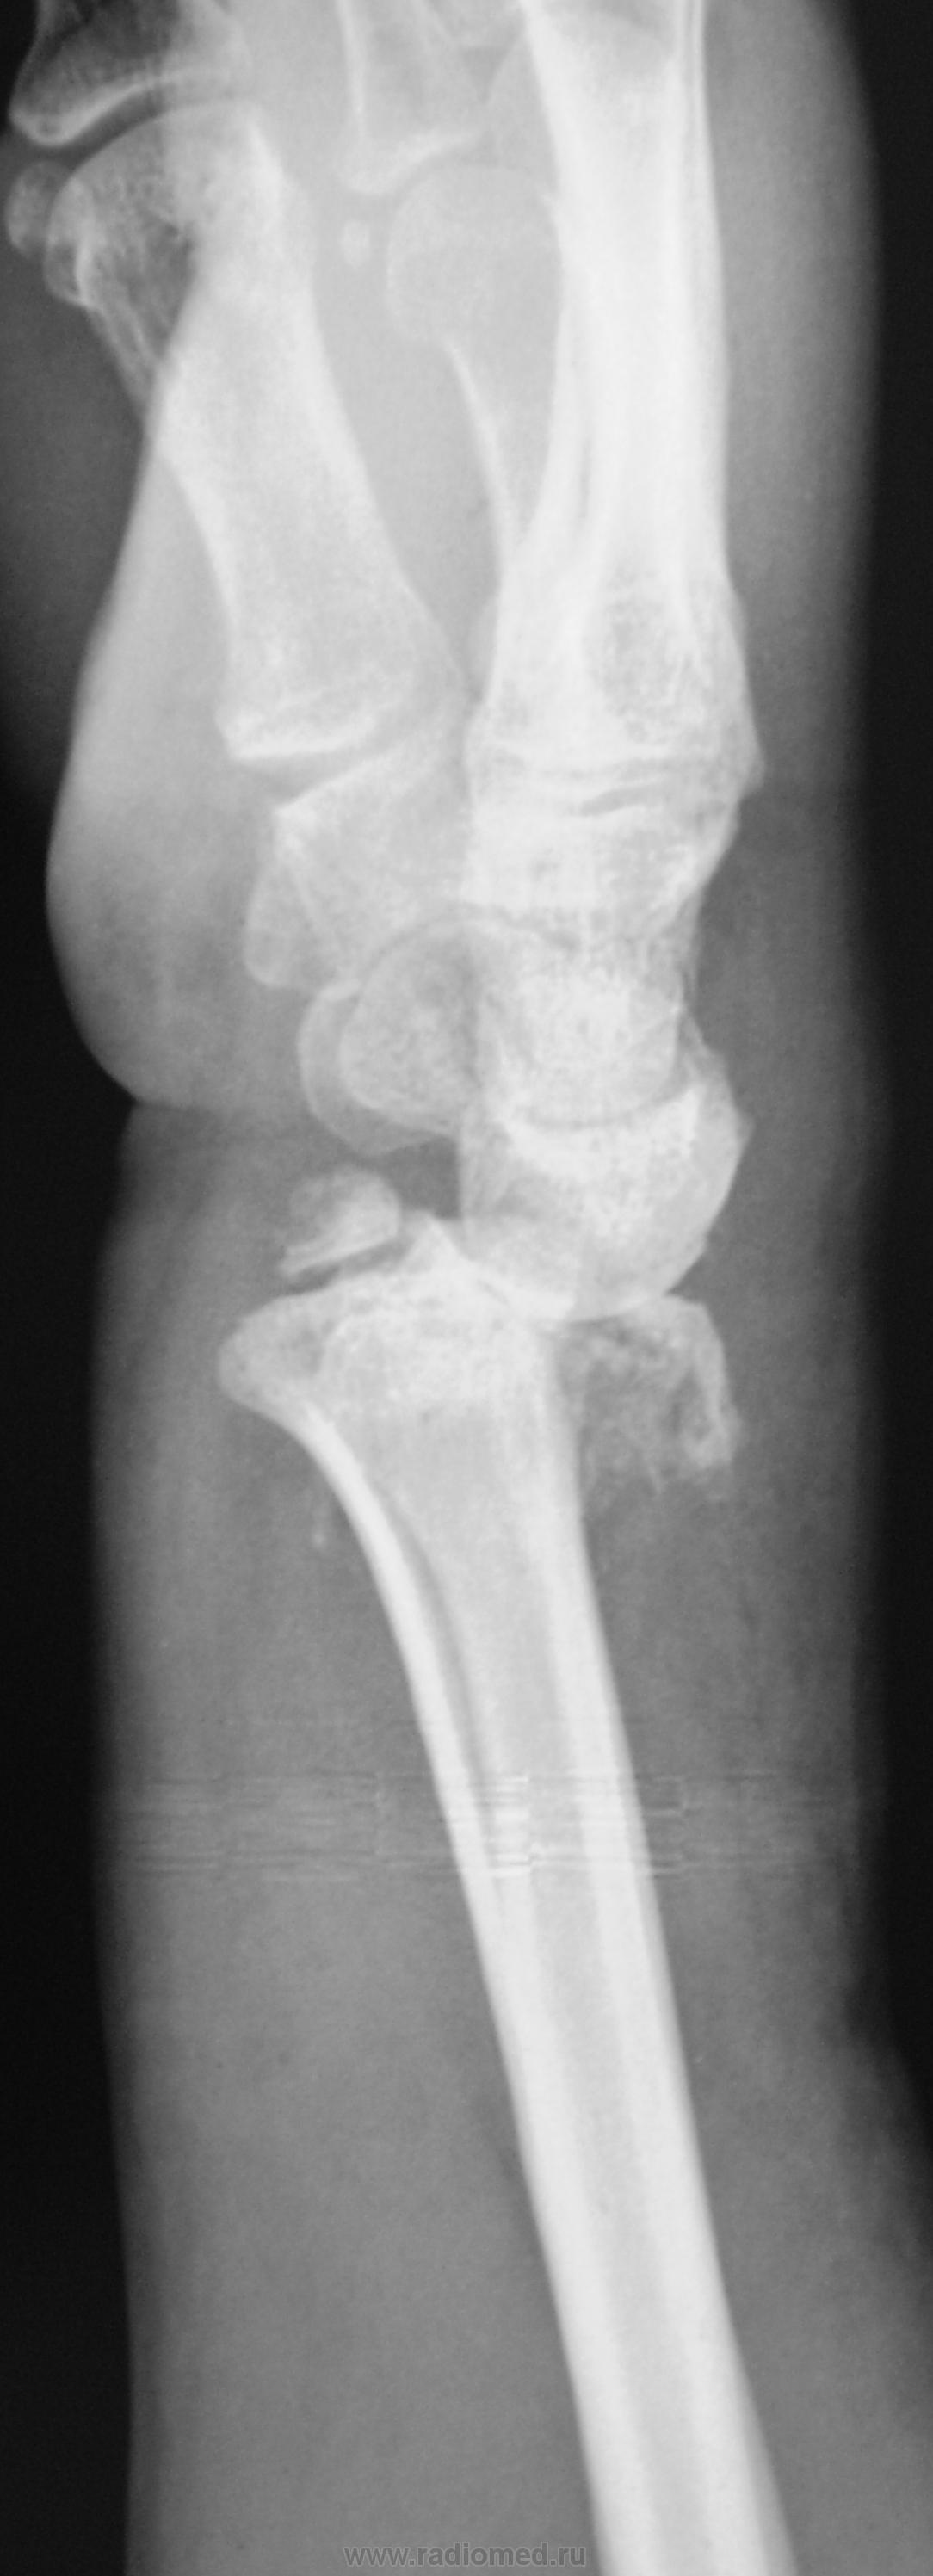

Травма. Пациент направлен на рентгенографию лучезапястного сустава.

перелом луча с отрывом шиловидного отростка. Вывих в лучезапястном суставе. Видимо упал с лестницы или неудачное голосование?

Истинный тыльный вывих кисти. Внутрисуставной оскольчатый перелом лучевой в типичном месте, перелом шиловидного отростка локтевой со смещением. А контроль после репозиции будет?

Сегодня был контроль, однако желаемое не достигнуто...

А "банкротом" может оказаться пациентка... Но это уже лирика)). Наше дело в данном случае маленькое: ДИНАМИКИ НЕТ, ВЫВИХ НЕ УСТРАНЕН. И всё))